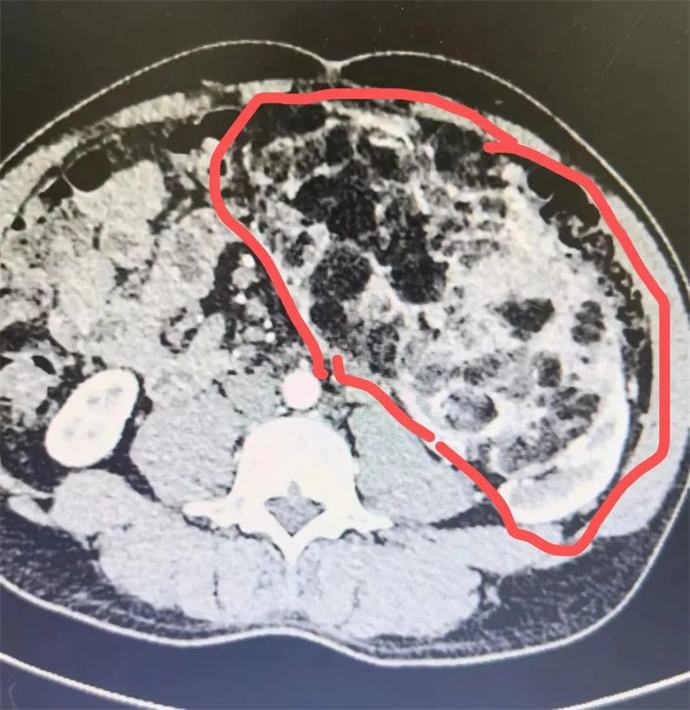

近日,我院泌尿外科會診一位四十多歲男性患者時發(fā)現(xiàn),該患者腹部有一巨大腫瘤,直徑近30cm,已將該患者胃、胰腺、脾臟及部分腸管擠壓移位,且腫瘤內(nèi)可見大量動靜脈畸形,存在極大的出血風險,一旦出血將危及患者生命,客觀告知患者及家屬相關病情后,患者及家屬憂心忡忡,基本的日?;顒佣夹挠形窇?,充分溝通后,轉(zhuǎn)入泌尿外科,擬行手術治療。

轉(zhuǎn)入泌尿外科后,強永春主任及專家組積極術前準備,仔細閱片,充分討論,明確此腫瘤來源為左側(cè)腎臟,多考慮為腎臟血管平滑肌脂肪瘤,俗稱“錯構瘤”。周莉護士長帶領護理組通過傾聽、解釋、鼓勵、提供支持、建立信任等來安撫患者的憂心忡忡,幫助他們更好地應對疾病??茖W、客觀的指導患者的術后康復。

錯構瘤屬于良性腫瘤,絕大多數(shù)錯構瘤患者沒有明顯的癥狀,一些比較大的錯構瘤,可能會出現(xiàn)局部壓迫癥狀或壓迫周圍臟器,出現(xiàn)相應的癥狀。腎錯構瘤最大的危害在于,體積較大的錯構瘤突然破裂時,患者會出現(xiàn)腰腹疼痛和血尿等癥狀,嚴重的大出血患者可以在腹部觸及到包塊,甚至有休克癥狀。因此當腫瘤直徑大于4cm時,一般會積極建議手術,減少自發(fā)破裂的風險。但該患者平素未行體檢,腫瘤已近30cm,因此貿(mào)然手術處理存在巨大的風險。

強永春主任帶領泌尿外科團隊積極協(xié)調(diào),提前預約腫瘤介入王忠主任,于術前行介入栓塞,減少術中出血風險;同時聯(lián)系輸血科提前術中備血;因腫瘤已侵及腎臟大部及腎臟血管,無法保留腎單位行腎部分切除,故先側(cè)臥位行后腹腔鏡下微創(chuàng)手術,游離并處理腎臟血管,確保切除時安全,再仰臥位行錯構瘤及腎臟切除;充分準備后,手術按預定方案如期進行,歷時6小時,成功拆除“定時炸彈”。目前患者已出院恢復了日常工作。